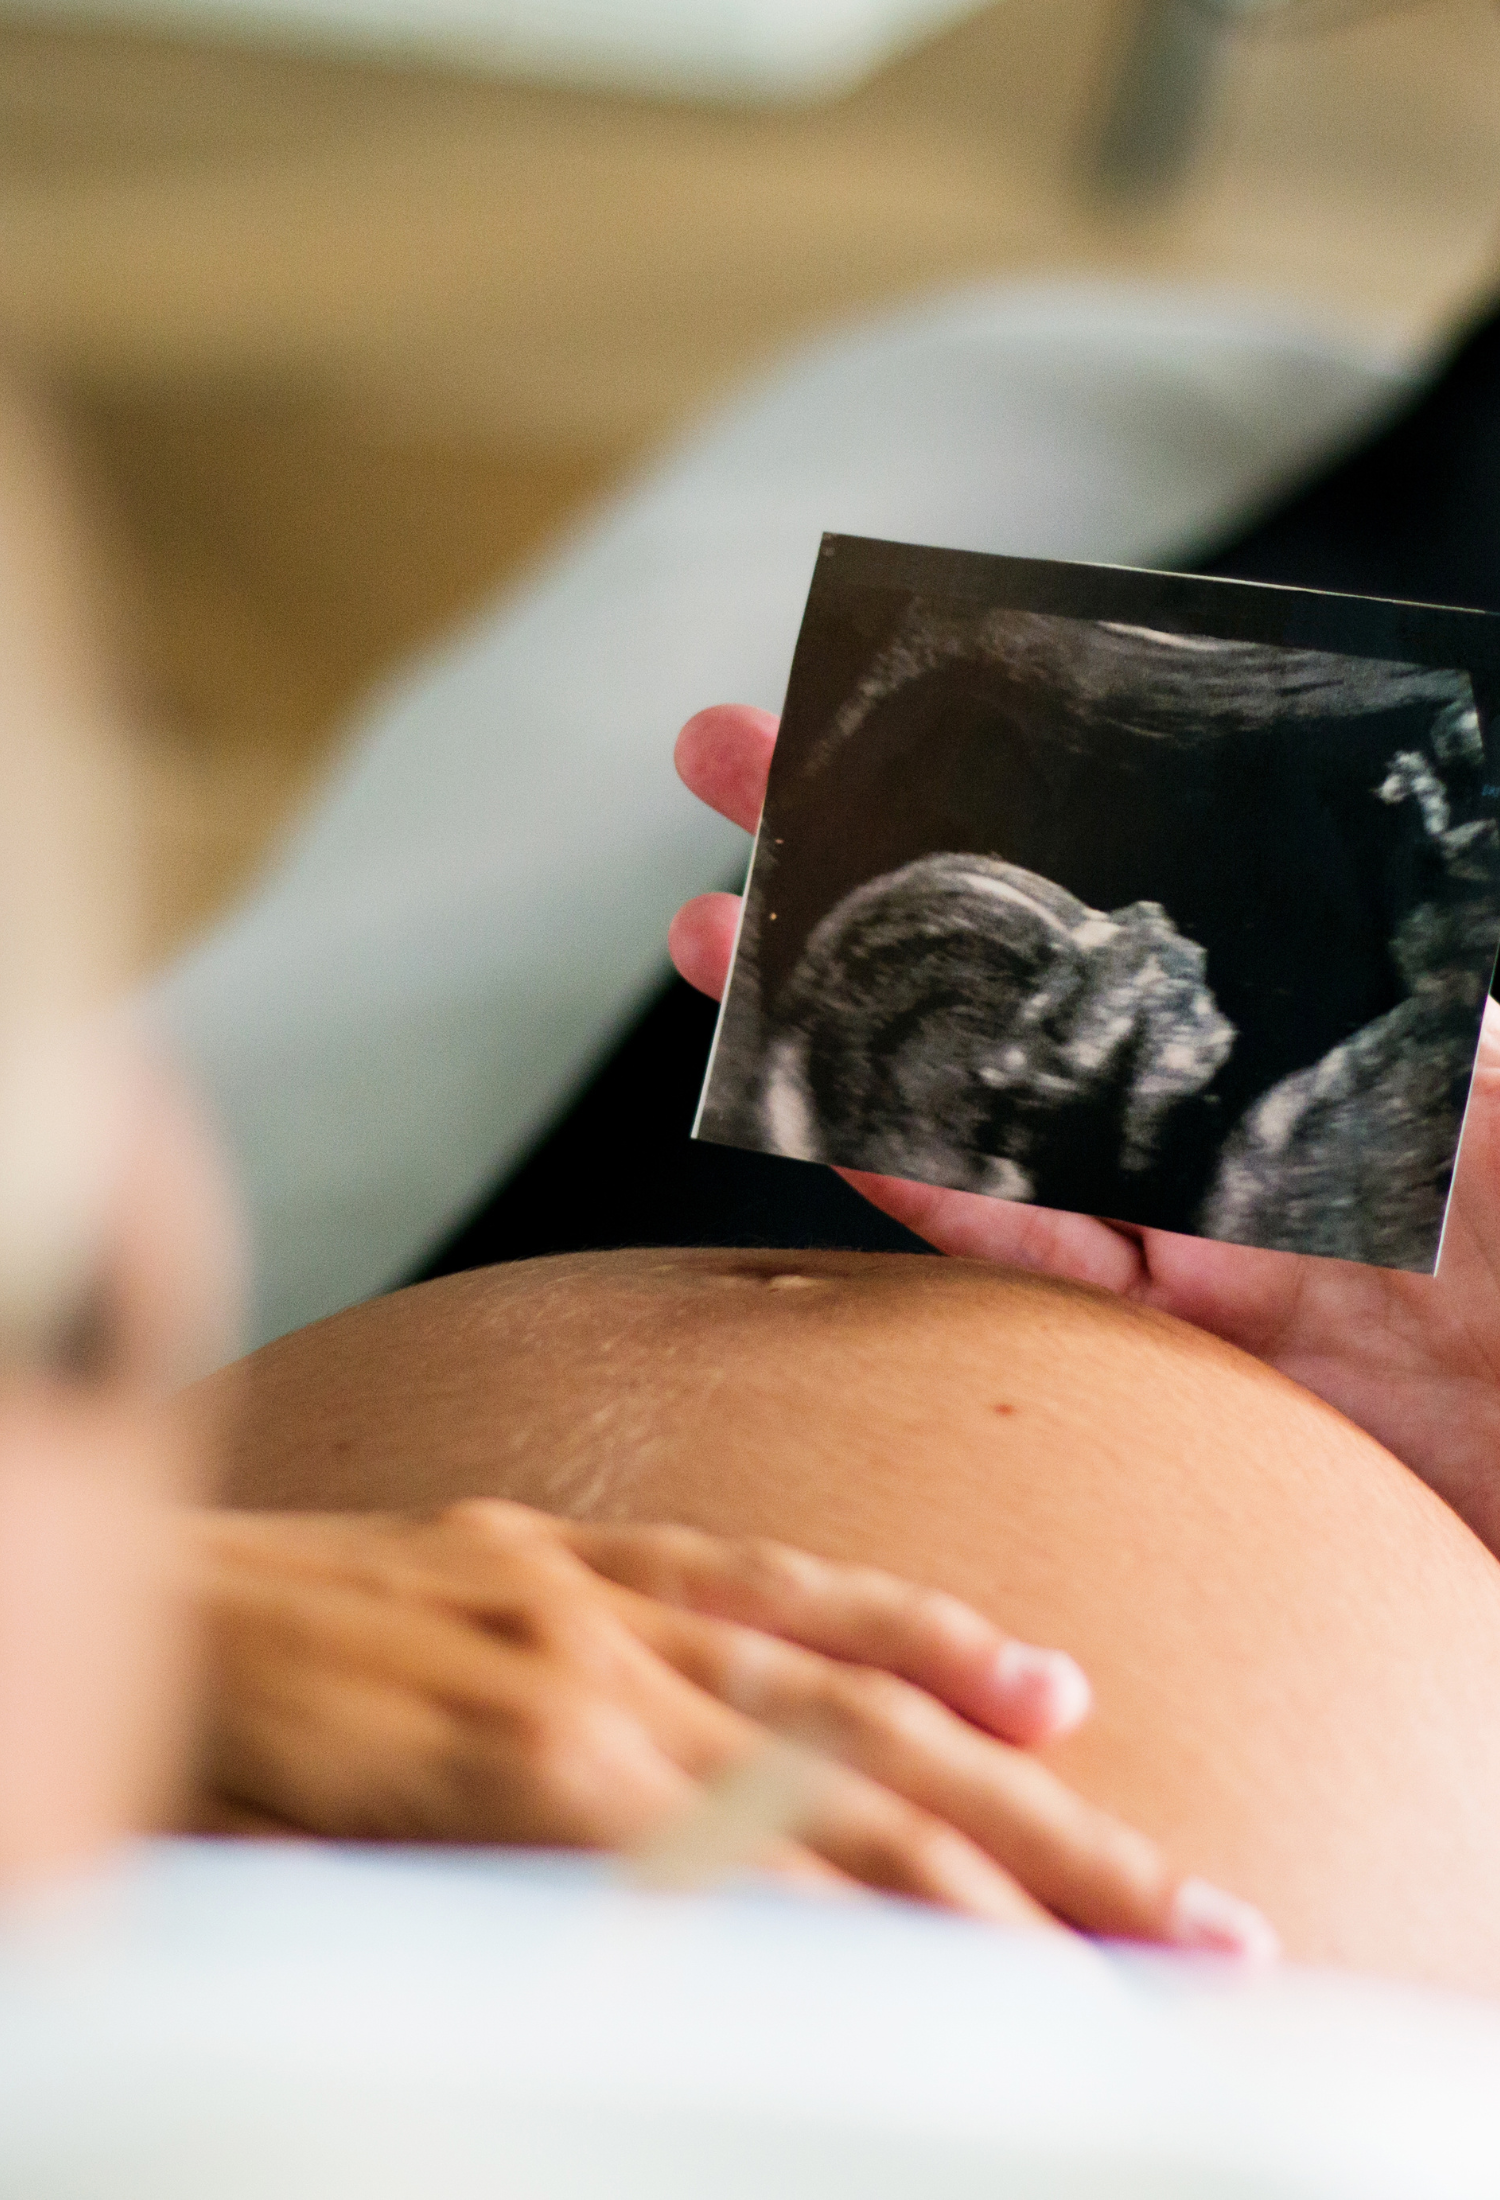

The fetal brain undergoes significant changes as a baby develops, so Oxford researchers are working to improve fetal ultrasound analysis and better standardise global measurements for fetal brain growth.

The Noble Group at the Institute of Biomedical Engineering looks at questions such as why ultrasound scanning and interpretation is so hard to learn, whether AI can simplify ultrasound and whether computers can mimic what a skilled sonographer can do.

One such collaboration proposed an automated framework for predicting age and neurodevelopmental maturation of a fetus based on 3D ultrasound brain images. This is particularly important, as accurate estimation of gestational age is essential to prenatal care.

The team, which included Professor Ana Namburete (founder of the Oxford Machine Learning in Neuroimaging Lab), Professor Alison Noble and Professor Aris Papageorghiou, developed a new feature-based model that had never before been attempted. Their analysis showed that the model did not just estimate chronological age, but also the neurodevelopmental stage of the fetus based on brain structure.

While fetal brain magnetic resonance imaging (MRI) offers detailed images of brain development, they are not used in the second trimester due to time and cost limitations. In this case, ultrasound (US) is then employed.

Expert sonographers are adept at reading ultrasound images, but MR images are easier for non-experts to interpret. By developing methods to synthesise MR-like fetal brain images from ultrasound ones, the researchers hope their framework can be useful when communicating ultrasound findings to both obstetricians and patients.